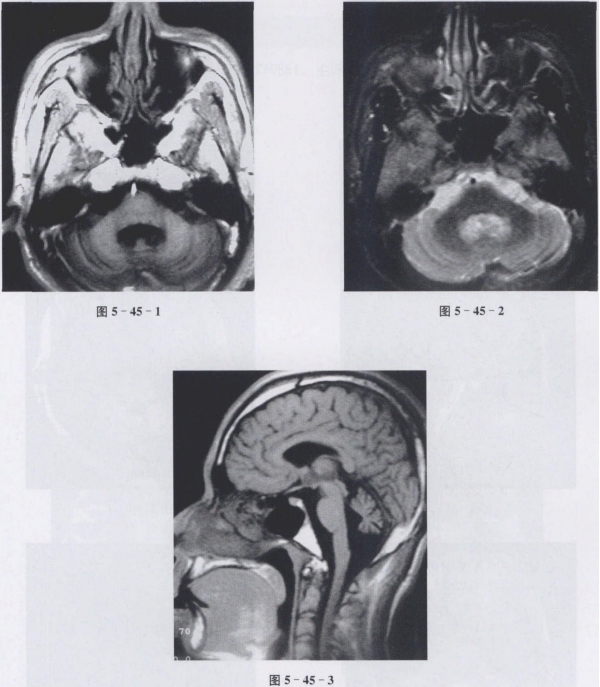

陈锡良的小脑萎缩,以后可能会失去行动能力。